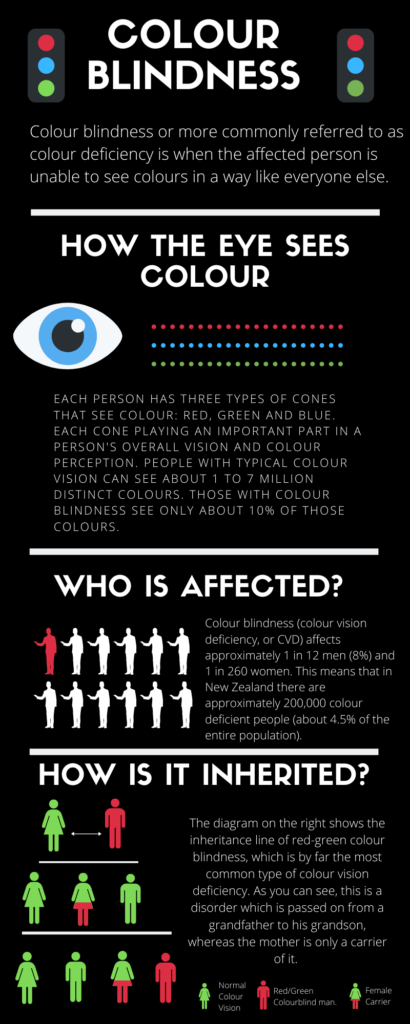

Colour blindness, more commonly referred to as colour deficiency, is when the affected person is unable to see colours in a way like everyone else.

Colour blindness (colour vision deficiency, or CVD) affects approximately 1 in 12 men (8%) and 1 in 260 women. This means that in New Zealand there are approximately 200,000 colour deficient people (about 4.5% of the entire population).

In the retina of your eye, there are two different cell types that detect light. They are referred to as rods and cones. Rods only picks up on light and dark, whereas cone cells are the ones picking up on the colours and are focused towards the centre of one’s vision.

Each person has three types of cones that see colour: red, green and blue. Each cone playing an important part in a person’s overall vision and colour perception. People with typical colour vision can see about 1 to 7 million distinct colours. Those with colour blindness see only about 10% of those colours.

Colour blindness can happen when one or more of the colour cone cells are missing, not working, or see a different colour shade than everyone else. The effects of colour vision deficiency can be mild, moderate or severe, for example, approximately 25% of New Zealand colour blind pupils currently leaving secondary school are unaware that they are colour blind, whilst 60% of sufferers experience many problems in everyday life.

Severe colour blindness occurs when all three cone cells are absent. Mild colour blindness happens when all three cone cells are present, but one cone cell does not work right.

Usually, colour blindness is due to genes inherited from your parents (in most cases, its mother to son) but sometimes in very rare cases, colour blindness is not because of your genes, but because of

The most common form of colour blindness is known as red/green colour blindness (protanopia). Being red/green colour blindness does not mean people mix up red and green, it means they mix up all colours which have some red or green as part of the whole colour. For example, a red/green colour blind person will confuse a blue and a purple because they can’t ‘see’ the red element of the colour purple.

Red-green colour blindness is the generic term used to describe the four different types of Red/green colour blindness. Protanopia (red-blindness), Protanomaly (red-weakness), Deuteranopia (green-blindness), and Deuteranomaly (green-weakness). More than 95% of all colour-blind people suffer from a red-green colour vision deficiency. Protanopia and Deuteranopia are the most common strands plaguing peoples visions.